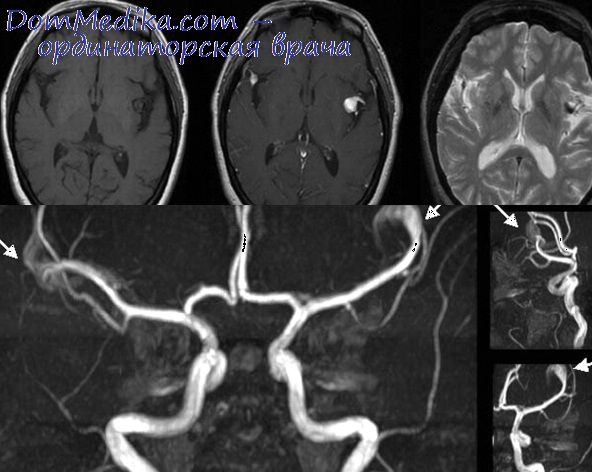

Анатомия: Задняя соединительная артерия мозга

Раздел: Фотоэссе